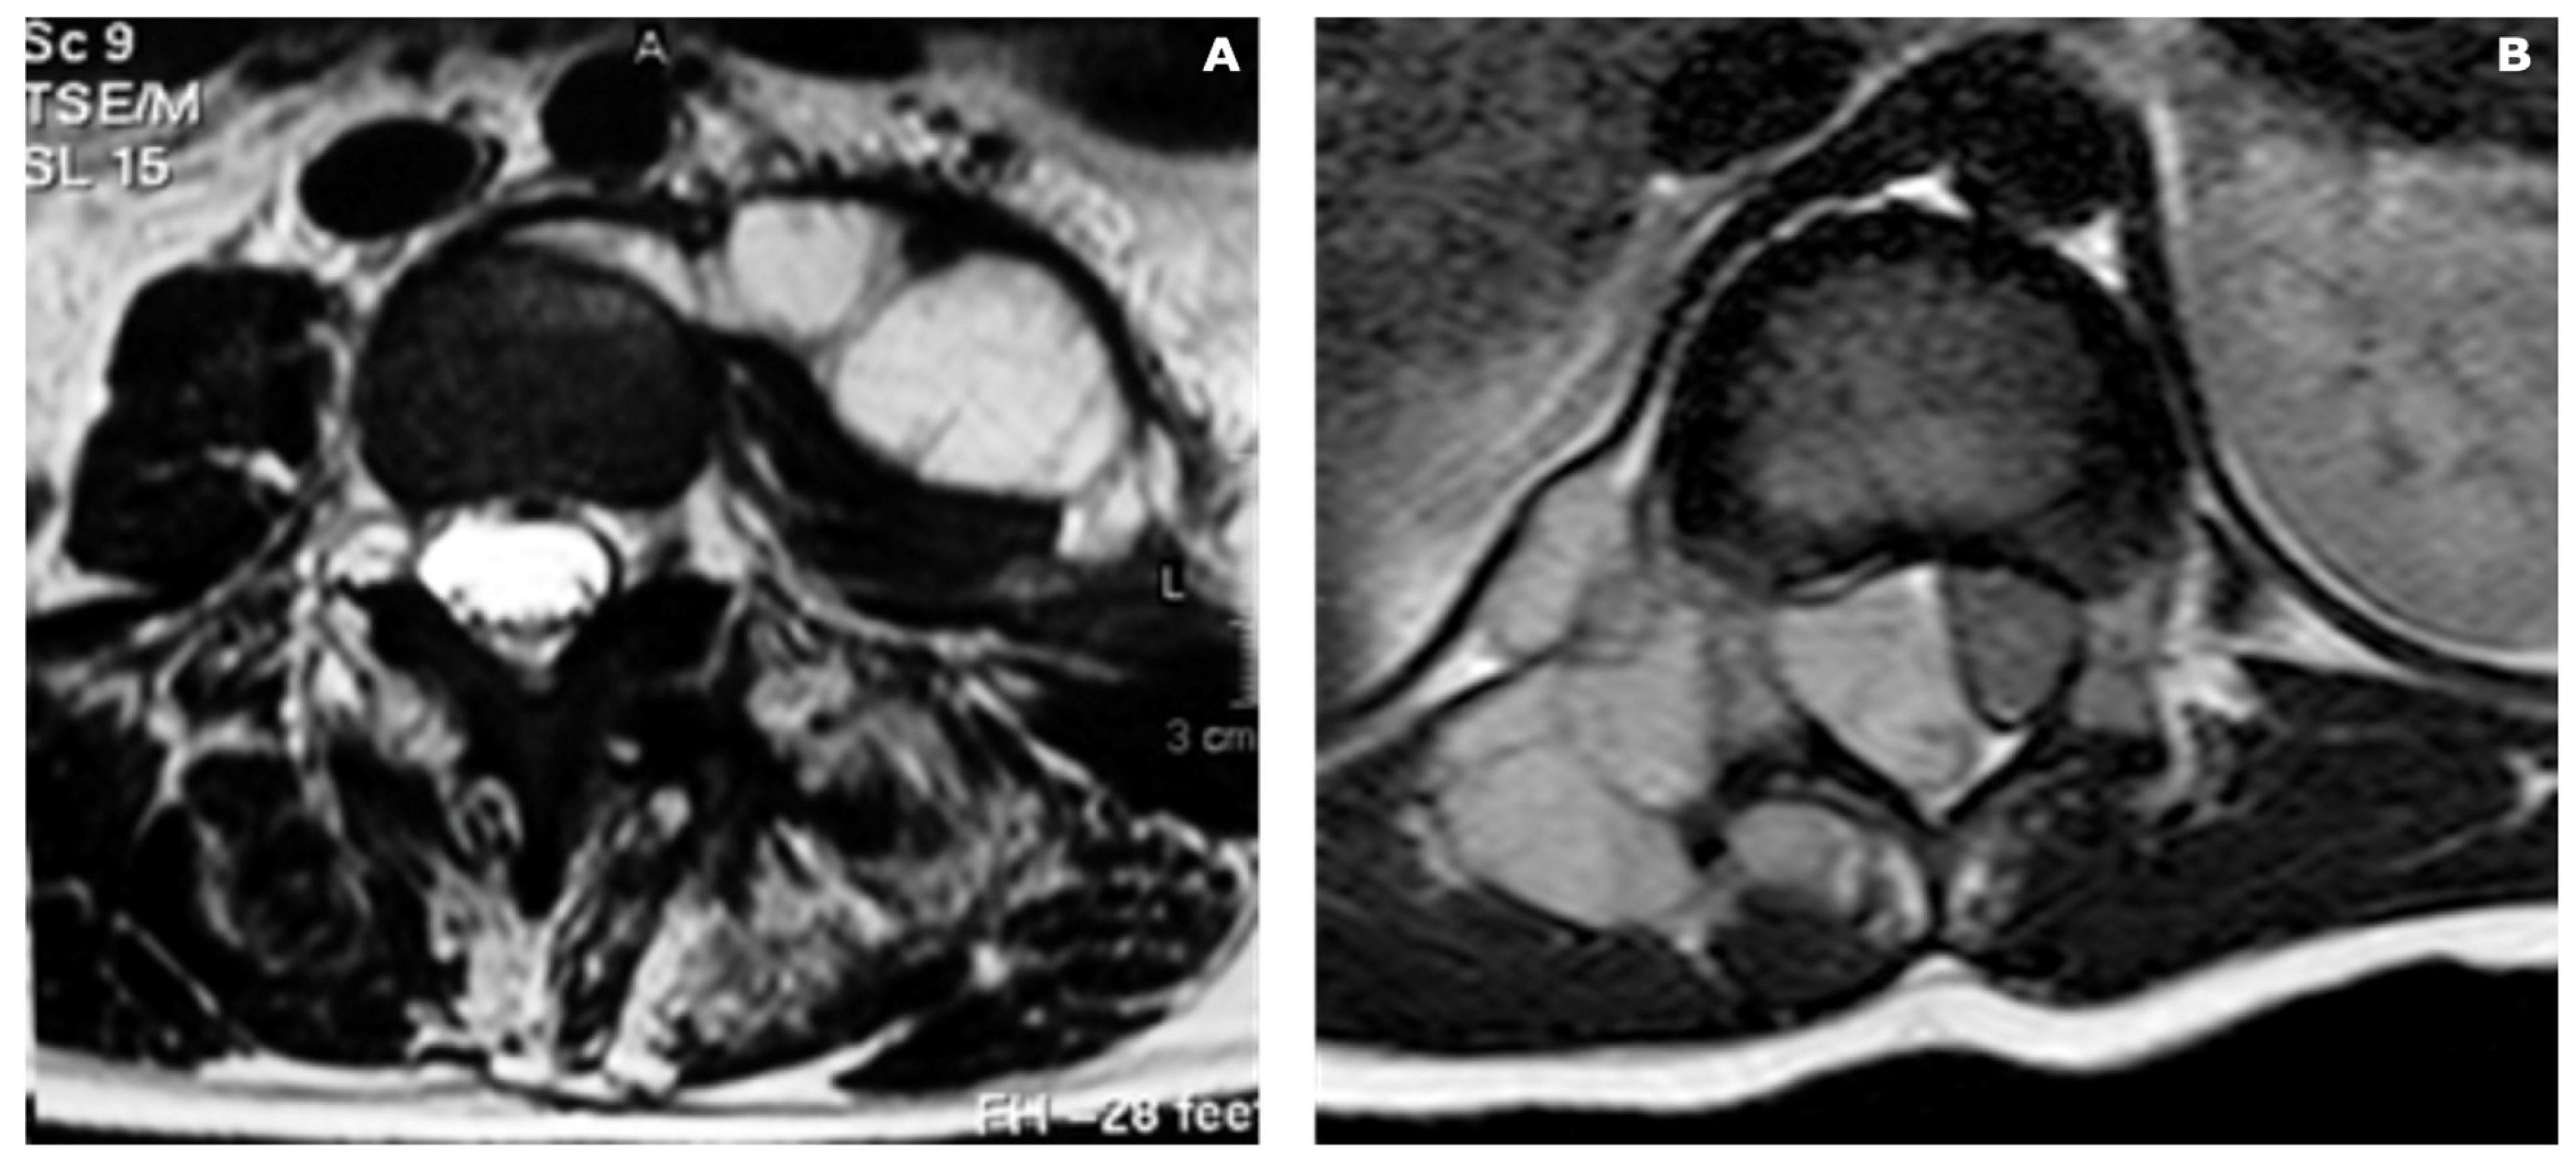

- -

- STAGE 1 => subtle changes, such as increased T2*-weighted signal intensity within the vertebral body, may be evident, indicating marrow edema or inflammation.

- -

- STAGE 2 => T1*-weighted: low signal; T2*-weighted: high signal in the bone marrow and intervertebral disc with heterogeneous enhancement may be observed, reflecting the presence of necrosis, abscess formation or granulation tissue [68,69]; the epidural abscesses show peripheral enhancement with central non-enhancing component.

- -

- STAGE 3 => T1*- and T2*-weighted low signal is due to vertebral collapse and endplate sclerosis.

- Hong, S.H.; Choi, J.Y.; Lee, J.W.; Kim, N.R.; Choi, J.A.; Kang, H.S. MR Imaging Assessment of the Spine: Infection or an Imitation? RadioGraphics 2009, 29, 599–612. [Google Scholar] [CrossRef] [PubMed]

- Chang, M.C.; Wu, H.T.H.; Lee, C.H.; Liu, C.L.; Chen, T.H. Tuberculous Spondylitis and Pyogenic Spondylitis: Comparative Magnetic Resonance Imaging Features. Spine 2006, 31, 782–788. [Google Scholar] [CrossRef]

- Ledermann, H.P.; Schweitzer, M.E.; Morrison, W.B.; Carrino, J.A. MR Imaging Findings in Spinal Infections: Rules or Myths? Radiology 2003, 228, 506–514. [Google Scholar] [CrossRef]

- Li, Q.; Song, J.; Li, X.; Luo, T.; Peng, J.; Lv, F.; Li, Y.; Huang, Z.; Wang, A. Differentiation of Intraspinal Tuberculosis and Metastatic Cancer Using Magnetic Resonance Imaging. Infect. Drug Resist. 2020, 13, 341–349. [Google Scholar] [CrossRef] [PubMed]

| Spinal Tuberculosis | Cervical and Lumbar spine; A single segment is involved | Collapse and destruction of the vertebra Loss of disc space “Gibbus deformity” Anterior wedging or kyphosis | Erosions, marginal sclerosis, and sequestra formation Lytic lesions Epidural and paraspinal involvement Spinal canal involvement Small bony fragment | relative Blood Flow (rBF) value < 4 relative Blood Volume (rBV) value < 3.5 | Early stage: hypointense on T1-weighted; hyperintense on T2-weighted (marrow edema, inflammation). granulomatous inflammatory response Chronic stage: hypointense on T1-weighted and on T2-weighted images (necrosis, abscess formation) Involvement of adjacent structures (spinal cord, nerve roots, and paraspinal tissues) | Heterogeneous enhancement (necrosis, abscess formation, or granulation tissue) | Early stage: restricted diffusion (low ADC values) Chronic stage: no diffusion restriction with high ADC values | Involvement of vertebral bodies and the related disc with rapid destruction Subligamentous spread with extension into the paraspinal soft tissue with abscesses, usually calcified Extension in epidural space with spinal cord or nerve compression Posterior elements of the vertebra are generally spared |

| Pyogenic Spondylitis | Cervical and Lumbar spine; A single segment is involved | Localized vertebral destruction Loss of disc height Paraspinal soft tissue swelling Bony sequestra, sclerosis, and vertebral collapse | Erosions, sclerosis, and sequestra formation Cortical destruction Sequestration and abscesses | relative Blood Flow (rBF) value < 4 relative Blood Volume (rBV) value < 3.5 | Early stage: hypointense on T1-weighted; hyperintense on T2-weighted (inflammation). granulomatous inflammatory response Chronic stage: hypointense on T1-weighted and on T2-weighted images (necrosis, abscess formation) Involvement of adjacent structures (spinal cord, nerve roots, and paraspinal tissues) | Enhancing inflammatory changes, abscesses, and granulation tissue Ring-enhancing abscesses with peripheral rim enhancement | Early stage: restricted diffusion (low ADC values) Chronic stage: no diffusion restriction with high ADC values | Involvement of vertebral bodies and the related disc with rapid destruction Subligamentous spread with extension into the paraspinal soft tissue with abscesses, usually calcified Extension in epidural space with spinal cord or nerve compression Posterior elements of the vertebra are generally spared |

| Neoplastic (Primitive) | Mostly Thoracic spine | Vertebral collapse Pathological fractures Abnormal spinal alignment | Destruction, erosion, sclerosis Presence of a bony mass Spinal canal involvement Erosion of the cortical bone Presence of spinal cord compression or nerve root impingement | relative Blood Flow (rBF) value > 4 relative Blood Volume (rBV) value > 3.5 | Location, size, extension Extent of spinal cord compression, evaluate nerve root involvement, and identify the presence of cystic or necrotic components within the tumor Various imaging features on MRI | Intense contrast enhancement in homogeneous or ring-like enhancement | Restricted diffusion (low ADC values) | Vertebral body and posterior elements involvement Preserved disc Halo Sign |

| Neoplastic (Metastasis) | Mostly Thoracic spine | Osteolytic, osteoblastic, or mixed lytic/blastic lesions Destructive bone lesions Loss of vertebral body height Pathologic fractures | Destruction, cortical thinning A soft tissue mass | relative Blood Flow (rBF) value > 4 relative Blood Volume (rBV) value > 3.5 | Location, size, extension Extent of spinal cord compression, evaluate nerve root involvement, and identify the presence of cystic or necrotic components within the tumor Various imaging features on MRI | Homogeneity, heterogeneity, or rim enhancement, can provide insights into the aggressiveness and vascularity of the metastatic lesions | Restricted diffusion (low ADC values) | Vertebral body and posterior elements involvement Preserved disc |